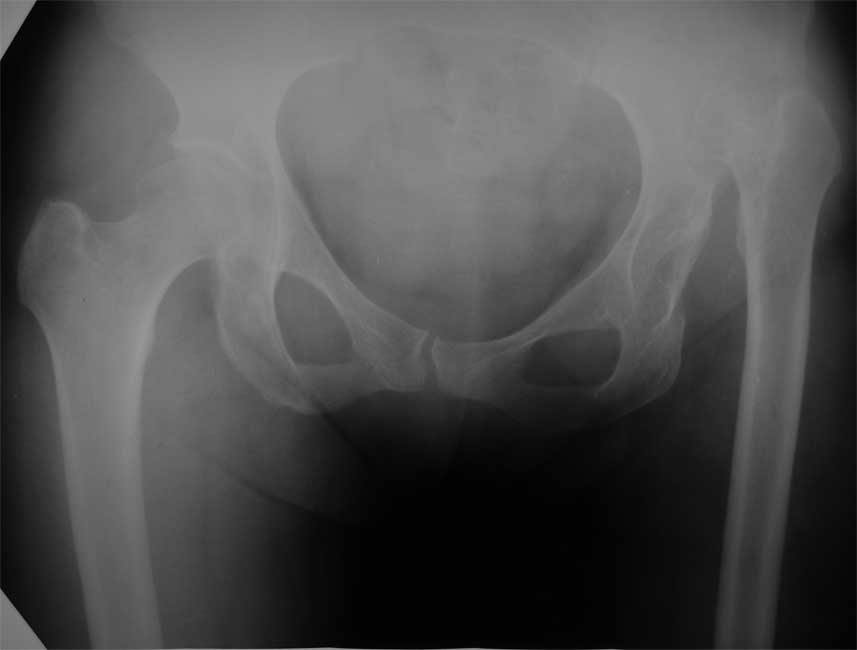

Госпитализирована пациентка 54 лет с высоким врожденным вывихом левого бедра. Основная жалоба - укорочение левой н/конечности (до 6 см), движения в полном объеме, боли в суставе нет. Вопросы: необходимо ли вообще выполнять THR или попытаться отговорить пациентку? Если делать, то как, дозированно низвести в аппарате, одномоментно с укорачивающей резекцией, потом удлинить бедро? насколько сильно пострадает коленный сустав (сейчас не беспокоит? Максим Агалаков, Е-бург.